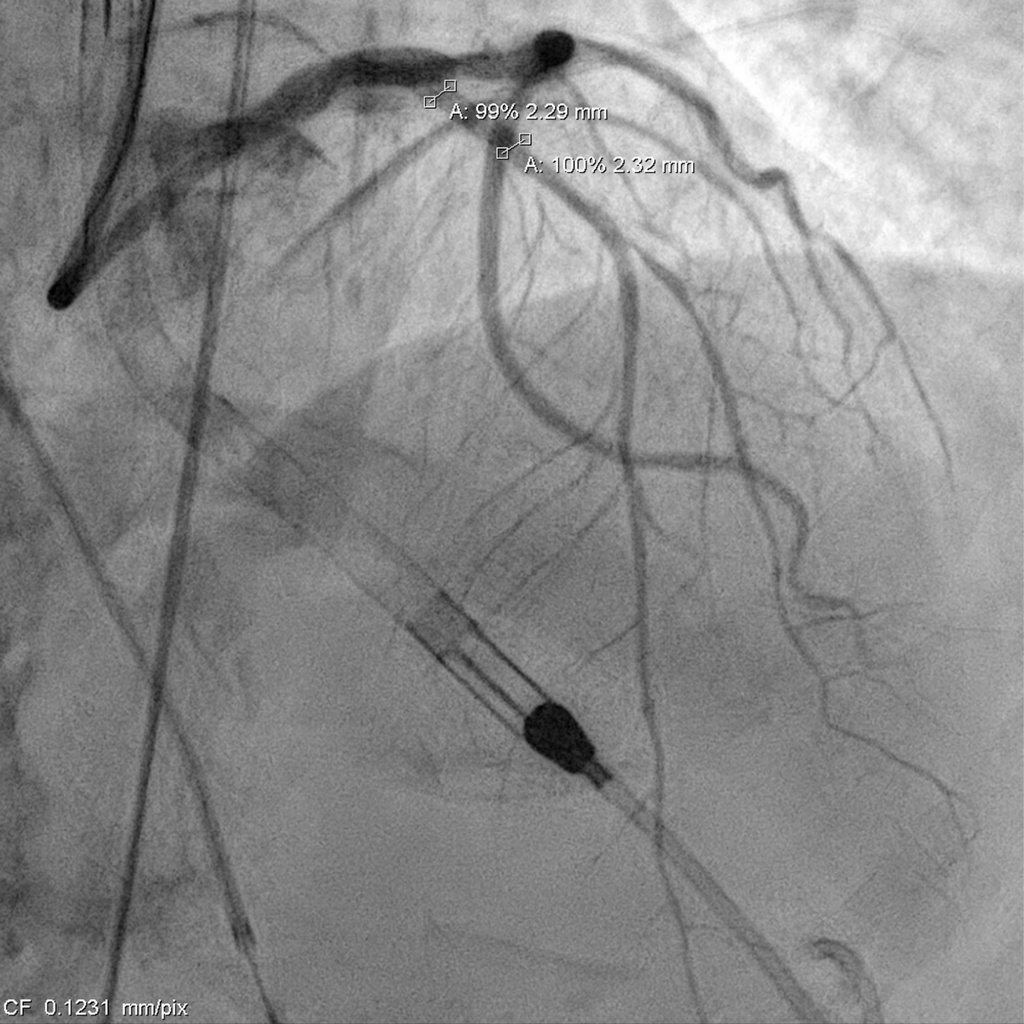

Relevant Catheterization Findings

Catheterization revealed a 95% distal left main stenosis with a calcified nodule protruding into the LAD and LCX ostia, a 99% proximal LAD lesion with an additional 90% stenosis after the first diagonal branch, non-critical LCX disease, and a 70% proximal RCA lesion with multiple critical PDA stenoses. The patient and family declined PCI in the cath lab, with a Syntax score of 40.

Impella support was established before the procedure. The LCA was engaged with an EBU 3.0 ¡¿ 7 Fr guide, and a SUOH-03 wire was advanced into the LCX. A 2.0 ¡¿ 20 mm balloon was inflated across the very tight LM–LCX lesion, but IVUS still could not cross, so rotablation was performed first. The SUOH-03 wire was exchanged for a Rota Floppy using a Caravel microcatheter, and a 2.0 mm burr successfully ablated the heavily calcified, angulated LM–LCX segment.After calcium modification, a Fielder FC wire was advanced into the LAD using a reverse-wire technique. Severe mid-LAD calcification required switching to a Rota Floppy wire, and a 1.25 mm burr was used for LAD rotablation. Bradycardia occurred during Rota, so a temporary pacemaker was inserted. A 2.25 ¡¿ 15 mm NC balloon was then inflated to 12 atm to further prepare the LAD.The LAD was stented with an Onyx 2.25 ¡¿ 22 mm DES (6–16 atm) and subsequently crushed with a 3.5 ¡¿ 12 mm NC balloon. LM–LCX was stented with an Onyx 3.5 ¡¿ 15 mm DES (11–12 atm). LAD was rewired with a Sion Blue supported by a Crusade dual-lumen catheter, and stent struts were opened using 1.5 ¡¿ 10 mm and 2.5 ¡¿ 15 mm balloons. LAD-P was post-dilated with a 2.5 ¡¿ 15 mm NC (10 atm), and LM–LAD with a 2.5 ¡¿ 15 mm NC (12–18 atm). Final kissing inflation with a 3.5 ¡¿ 12 mm NC and 2.5 ¡¿ 15 mm NC balloons achieved optimal flow.The Impella was removed under stable hemodynamics, and the access site was closed with two Perclose devices without bleeding.